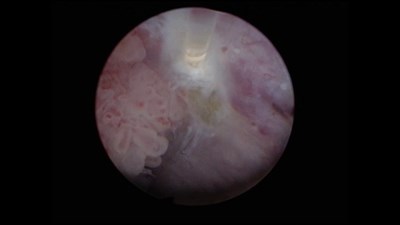

Сорокин Н.И. - «Диагностика и эндоскопическая визуализация опухоли мочевого пузыря»

Выступление на X Научно-практической конференции «Лопаткинские чтения» 16 февраля 2024 года.